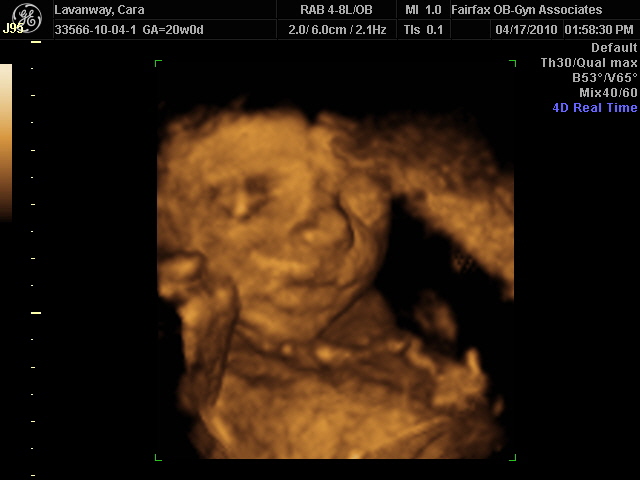

3d 4d Ultrasound Virginia

Virginia 3d 4d Ultrasound Fairfax Ashburn Youtube